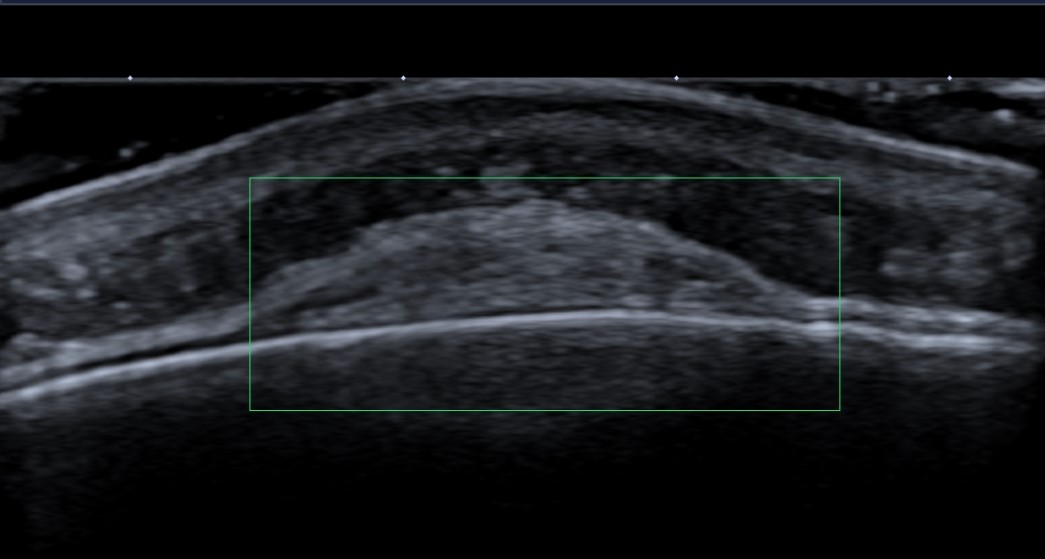

Forehead lump, mobile, soft and fluctuant, persistent for more than 1 year.

Solid echogenic mass between the periosteum and galea aponeurosis. It has a relatively flat base and smooth convex displacement of galea aponeurosis. No vascularity. Underlying bony cortex is smooth.

Subgaleal lipoma.